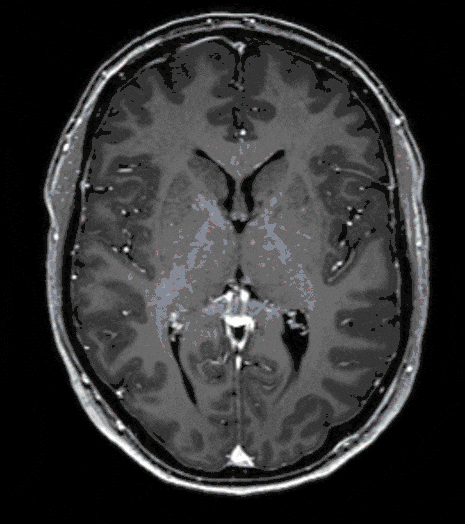

Glioblastoma

Glioblastomas are among the most aggressive tumors of the brain and usually develop directly from healthy cells but can also arise secondarily from benign precancerous lesions (see Gliomas).